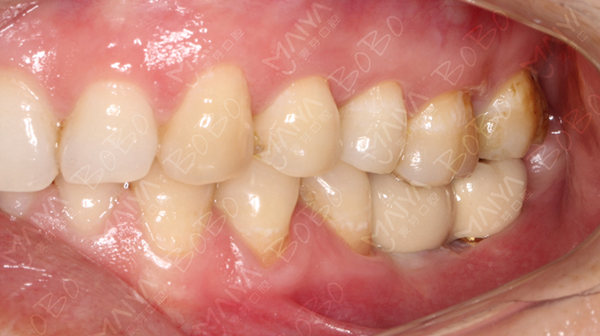

种植完成后的牙齿情况

牙齿拔了或掉了后能不种吗?深圳麦芽口腔种植医师团队告诉你:"拔而不种,问题严重。"牙齿拔了后,左右两边的牙齿就会互相靠过来,上面对准的那颗牙齿由于一直没有机会咬合,会慢慢发生移位,最后影响咀嚼功能,甚至导致咬颌关节疼痛、咬合困难等。近年来随着经济和生活水平的提高,"牙病不算病""老掉牙是正常现象"这样的旧观念已经被人们逐渐摒弃,越来越多的人对口腔健康要求越来越高。